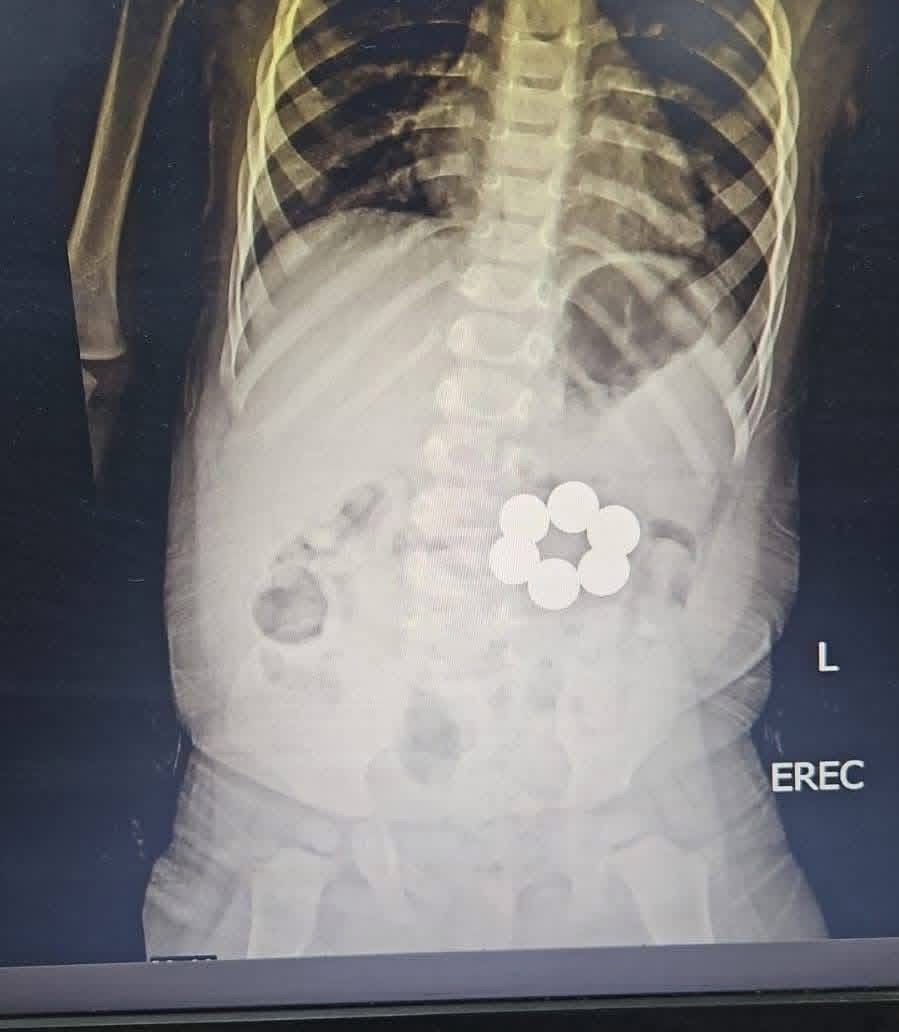

إنقاذ رضيع ابتلع 6 قطع مغناطيس في جراحة دقيقة بمستشفى الأطفال الجامعي بالمنصورة

شهدت وحدة الجهاز الهضمي بمستشفى الأطفال الجامعي بالمنصورة نجاحًا طبيًا جديدًا، بعد تمكن فريق طبي متخصص من إنقاذ طفل رضيع يبلغ من العمر عامًا و4 أشهر، إثر ابتلاعه 6 قطع مغناطيس ذات قوة جذب عالية، في واقعة خطيرة كادت أن تهدد حياته.

ونجح الفريق الطبي في استخراج جميع القطع المغناطيسية بدقة عالية خلال وقت قياسي، دون تسجيل أي مضاعفات أثناء أو بعد الإجراء، مع الحفاظ الكامل على سلامة الجهاز الهضمي للطفل.